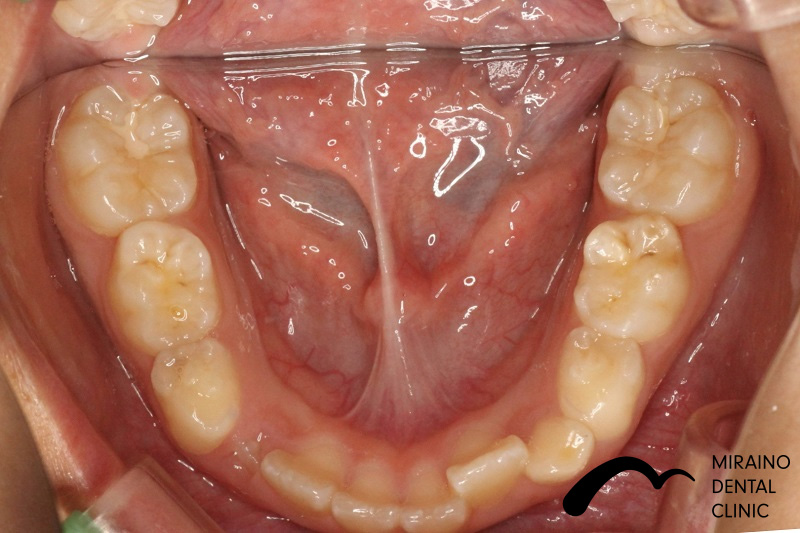

子どもの矯正の症例

Case2

before

after

Case3

Case4

Case5